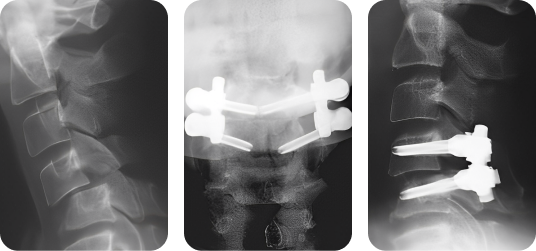

Клинический пример 2

- Пациент:

- Женщина, 62 года

- Диагноз:

- Нестабильность сегмента С1-С2 на фоне ревматоидного артрита

- Лечение:

- Выполнена трансартикулярная фиксация сегмента С1-С2 винтами и крючком Neon™.